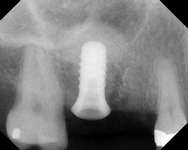

Figure 1G Radiographic confirmation of bone regeneration 8 months after surgery. Figure 1H Radiographic confirmation of implant osteointegration into the new bone 14 months after the initial surgery. Figure 1I. Final implant-supported restoration.

Figure 3D The site 6 months after surgery, confirming integration. Figure 4A Preoperative radiograph showing ridge resorption.

Figure 4B Radiographic confirmation of graft confinement and incremental addition.

Figure 4C Radiographic view of implant placed simultaneously with sinus bone grafting in site No. 3. Figure 4D Radiographic confirmation of the re-establishment of the sinus floor. Figure 4E Final implant-supported restoration.